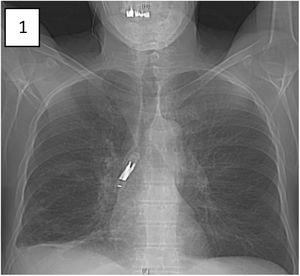

Non-cystic fibrosis bronchiectasis, a condition that remains relatively underrecognized, has garnered increasing research focus in recent years. This scientific interest has catalyzed advancements in diagnostic methodologies, enabling comprehensive clinical and molecular profiling. Such progress facilitates […]